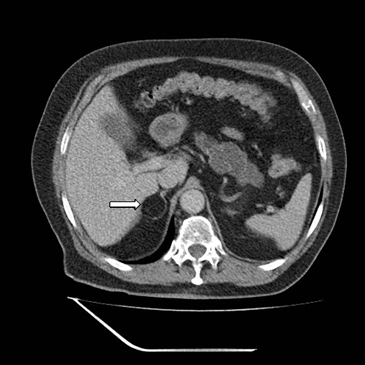

En la TC no contrastada las glándulas suprarrenales normales son homogéneas y simétricas, con una densidad muy similar a la del parénquima renal adyacente (Figura 1 a). Con un medio de contraste ev la glándula suprarrenal se opacifica en forma homogénea, similar al hígado o al bazo (Figura 1 b). Si la cantidad de tejido adiposo retroperitoneal es abundante las glándulas suprarrenales pueden aparecer enteramente rodeadas por grasa y su delimitación es más fácil (Figura 2 a); lo inverso ocurre en pacientes muy delgados con escasa grasa retroperitoneal (Figura 2 b). En RM, en secuencias ponderadas en T1 y T2 convencionales tienen una intensidad de señal homogénea, hipointensa respecto de la grasa adyacente e iso o hipointensa con respecto del parénquima hepático (Figura 3 a y b). En los cortes coronales se aprecia mejor la forma y la posición de las glándulas suprarrenales (Figura 3 c).

Figura 1. Glándula suprarrenal normal en tomografía computada. Cortes axiales de tomografía computada, donde se identifica la morfología normal de la glándula suprarrenal derecha (flecha) en fase no contrastada (a), y tras el uso de medio de contraste endovenoso (b).